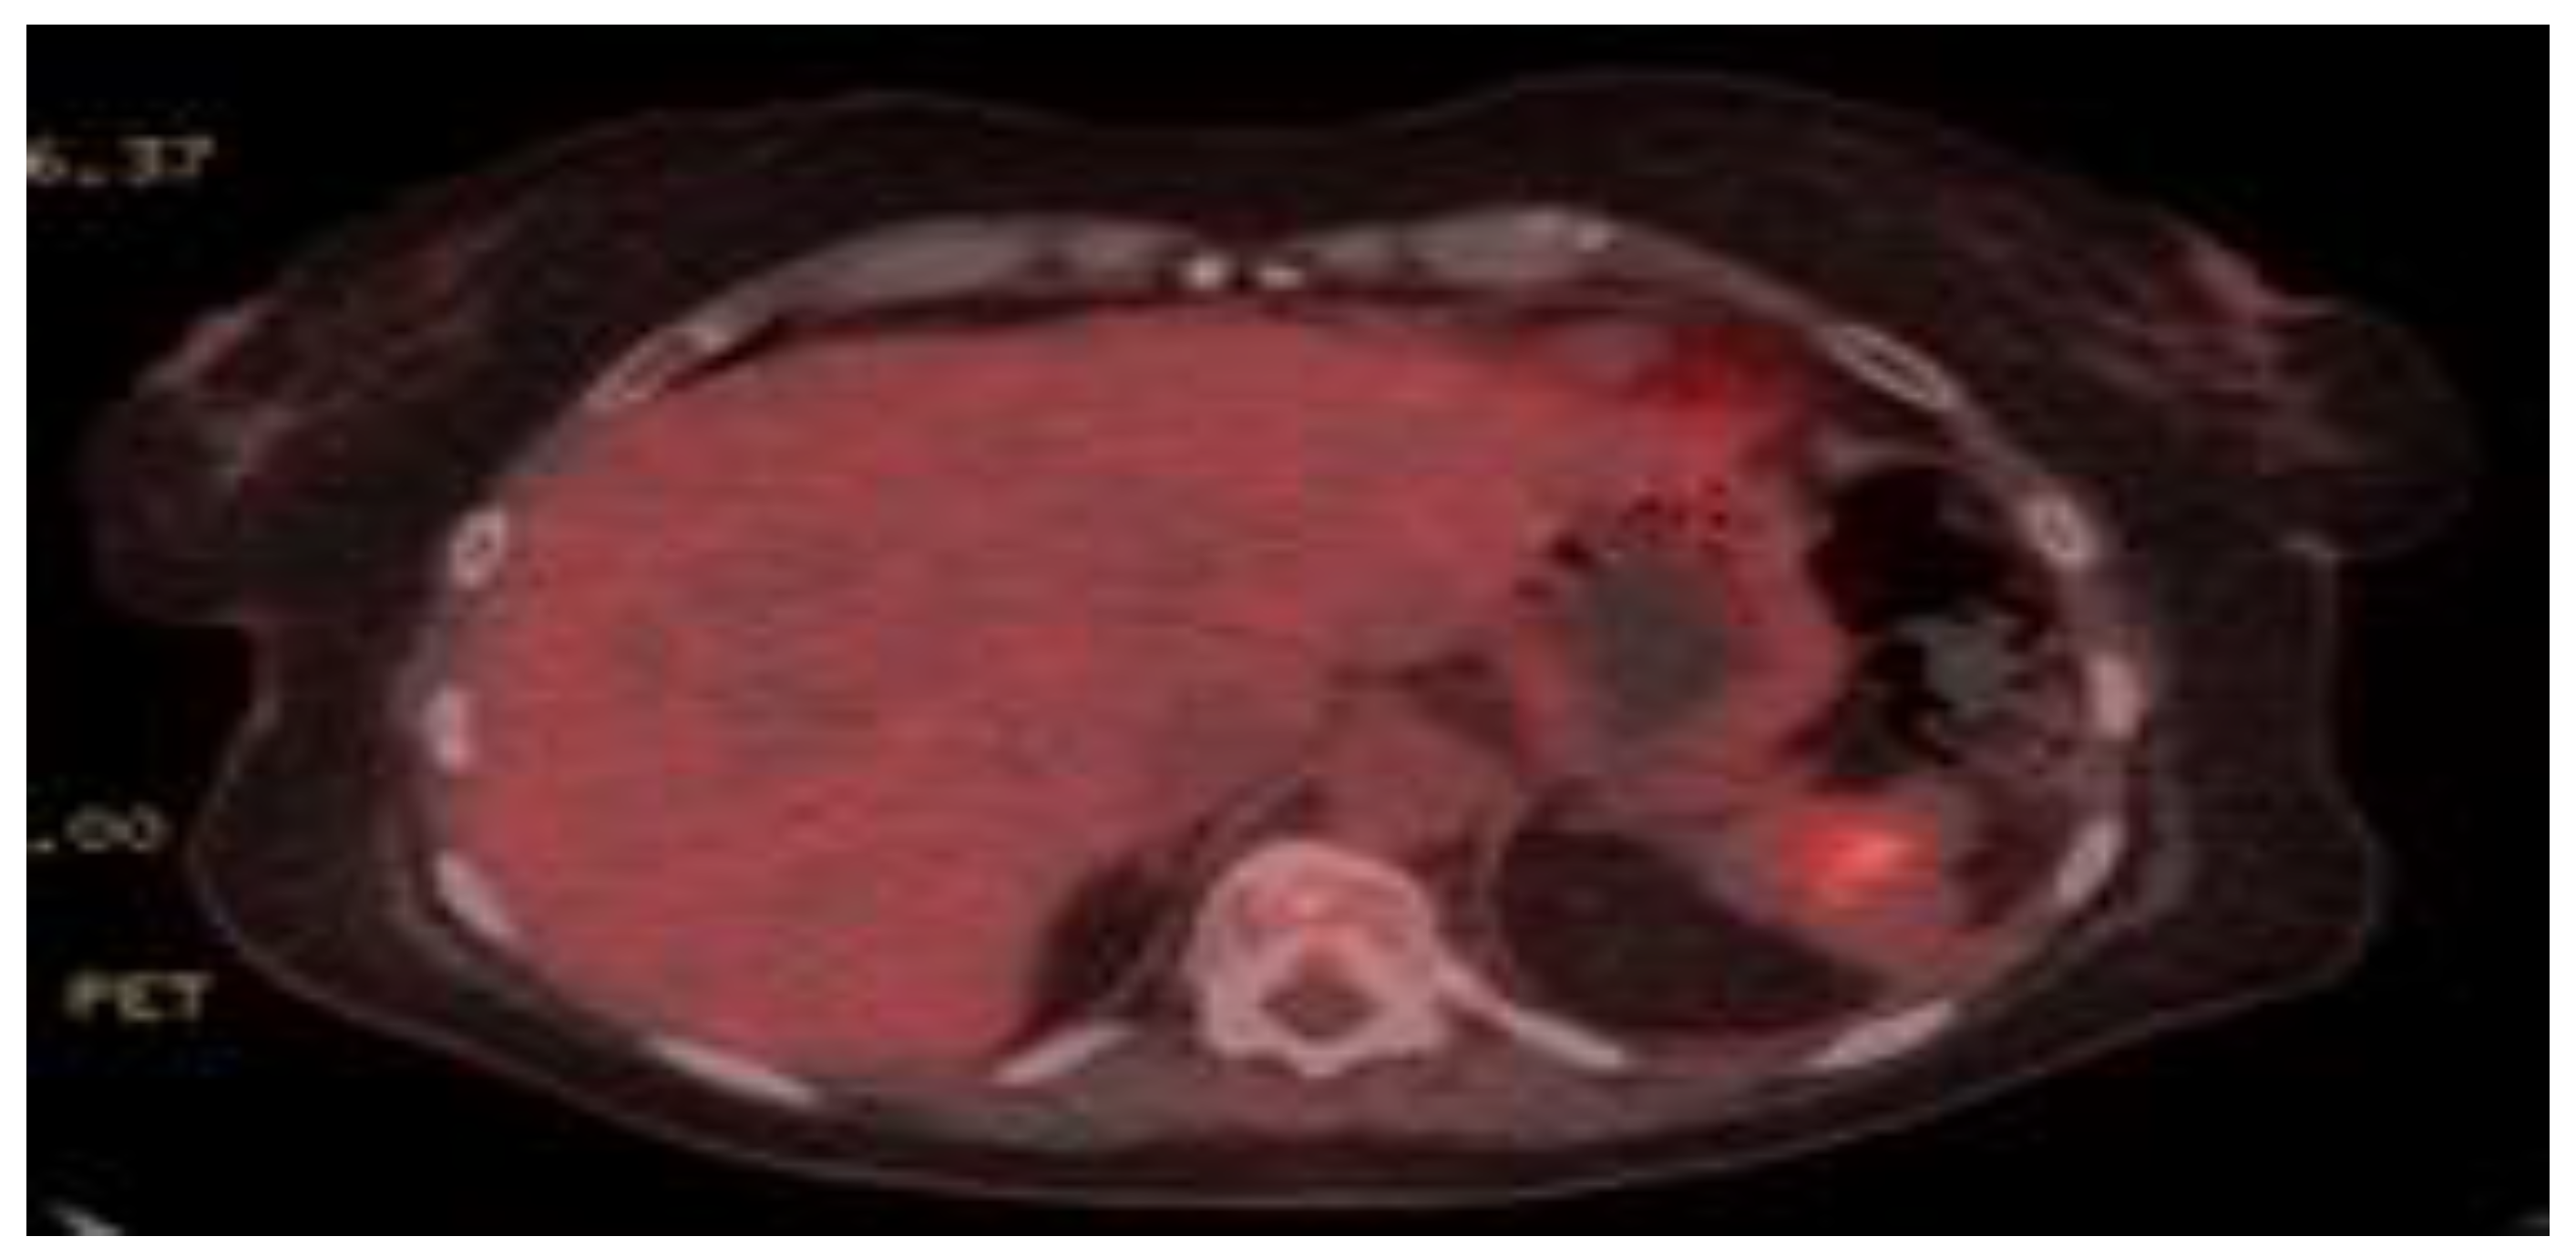

Gastro-Splenic Fistula Related to Large B Cell Lymphoma

2. Case Presentation